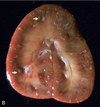

What are the molecular and morphologic changes of the image? ( MDx)

Clinical history and signs: 3 week old puppy, anorexia, dypsnea, abd pain upon palpation, normal rectal temperature

Multifocal, acute renal necrosis and hemorrhage or necrohemorrhagic nephritis

What is the etiology?

Clinical history and signs: 3 week old puppy, anorexia, dypsnea, abd pain upon palpation, normal rectal temperature

Canine herpesvirus-1 (CHV-1)

- red spots are from the virus targeting endothelium

What is the pathogenesis?

Clinical history and signs: 3 week old puppy, anorexia, dypsnea, abd pain upon palpation, normal rectal temperature

Transmission CHV-1 to pup at birth >incubation period of up to 1 week > virus replicates at temperature lower than 37C (98.6F) > endothelial cell tropism > multifocal necrosis in numerous organs